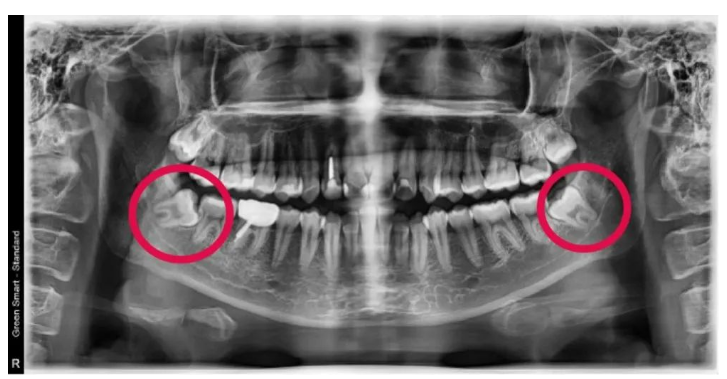

如果照镜子没发现自己有智齿?嘿嘿,先别高兴太早,有可能真的还没长智齿,也有可能是智齿阻生了。

阻生智齿经常会闹出点事情来,比如使劲顶着前面的牙齿,最终把前面的牙齿顶坏。这种情况一般不会疼,只是偶尔牙齿酸酸的,大多数不会被重视。

直到有一天,喝口热水突然疼得一激灵,才捂着半边脸去看医生,此时智齿前面的这颗牙多半已经“出师未捷身先死”,被智齿顶出了一个大洞。

又比如长歪的智齿只露了一点小头,周围的牙龈像个大口袋一样,紧紧包住智齿。由于智齿处在一个不上不下的位置,清洁工作很难做到位,食物残渣就一直往牙龈里面塞啊塞啊……最终导致牙龈红肿发炎,继续发展会形成脓肿,张大嘴和吞咽食物的时候就特别疼。